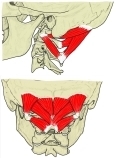

「 頭を後方に引き、一側が働くと収縮した筋と同じ側に回転する。 」 ( 日本人体解剖学 )

The rectus capitis posterior major ( or rectus capitis posticus major, both being Latin for larger posterior straight muscle of the head ) arises by a pointed tendon from the spinous process of the axis, and, becoming broader as it ascends, is inserted into the lateral part of the inferior nuchal line of the occipital bone and the surface of the bone immediately below the line.

A soft tissue connection bridging from the rectus capitis posterior major to the cervical dura mater was described in 2011. Various clinical manifestations may be linked to this anatomical relationship.[1] It has also been postulated that this connection serves as a monitor of dural tension along with the rectus capitis posterior minor and the obliquus capitis inferior.

As the muscles of the two sides pass upward and lateralward, they leave between them a triangular space, in which the rectus capitis posterior minor is seen.

Its main actions are to extend and rotate the atlanto-occipital joint.